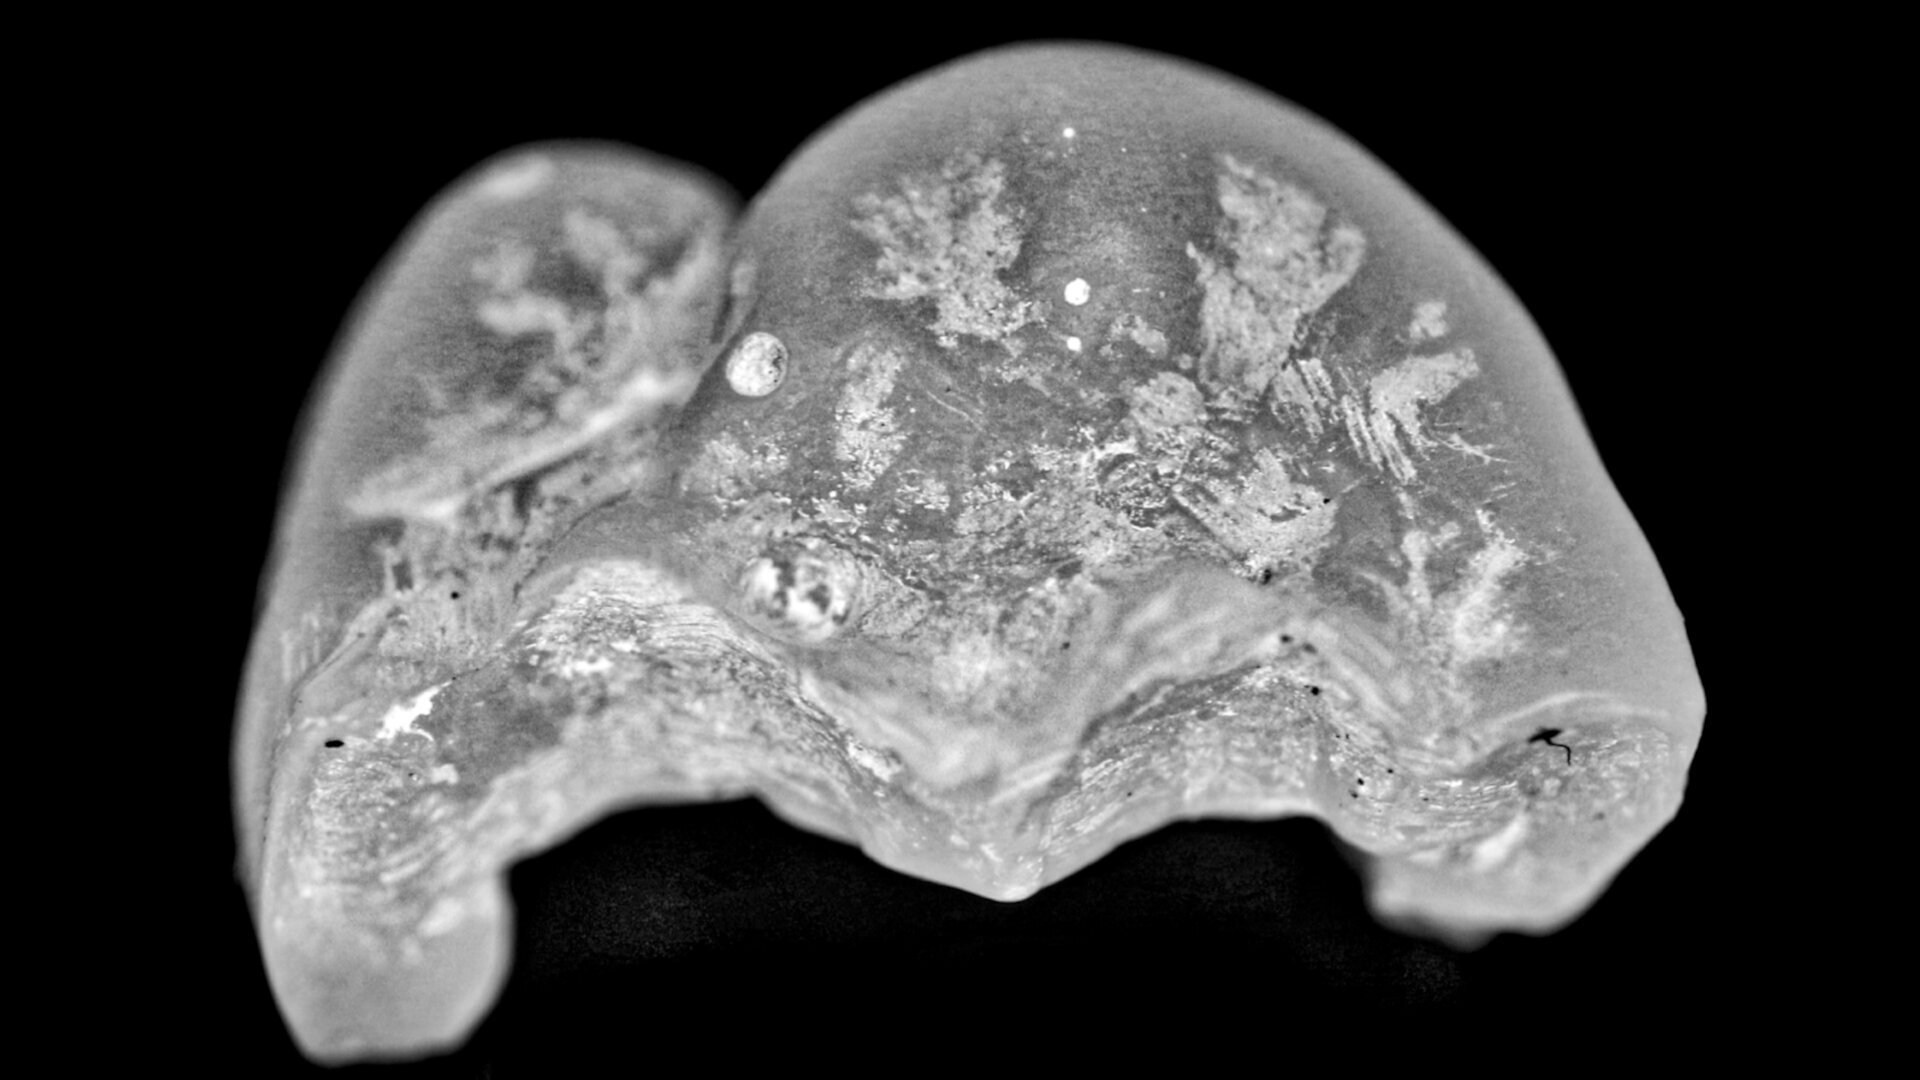

Provisional restoration. (All images: Les Kalman)

Three extracted and undamaged human molars were selected at random. A handheld tool was used to support each molar. To impress each tooth, a sectional tray (TempTray, Clinician’s Choice Dental Products) and provisional material (Template, Clinician’s Choice Dental Products) were used. Preparation of the teeth was performed for a four-surface onlay, either mesial-occlusaldistal-lingual or mesial-occlusal-distal-buccal (Fig. 1). The provisional matrix was loaded with a bis-acrylic composite resin (Integrity, Dentsply Sirona) and was placed on the prepared tooth. A standard four-surface provisional restoration was fabricated, shaped and polished (Fig. 2).